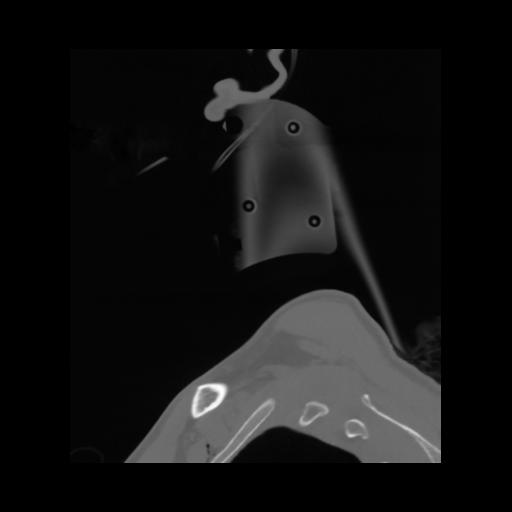

14 P.BLANDAS,,Sagittal,2.000,P.BLANDAS,Sagittal,